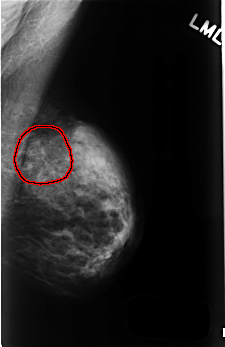

C_0509_1.LEFT_MLO

LEFT_MLO LINES 4504 PIXELS_PER_LINE 2920 BITS_PER_PIXEL 12 RESOLUTION 50 OVERLAY

FILE: C_0509_1.LEFT_MLO.OVERLAY

TOTAL_ABNORMALITIES 1

ABNORMALITY 1

LESION_TYPE CALCIFICATION TYPE AMORPHOUS DISTRIBUTION SEGMENTAL

ASSESSMENT 4

SUBTLETY 2

PATHOLOGY BENIGN

TOTAL_OUTLINES 1

BOUNDARY